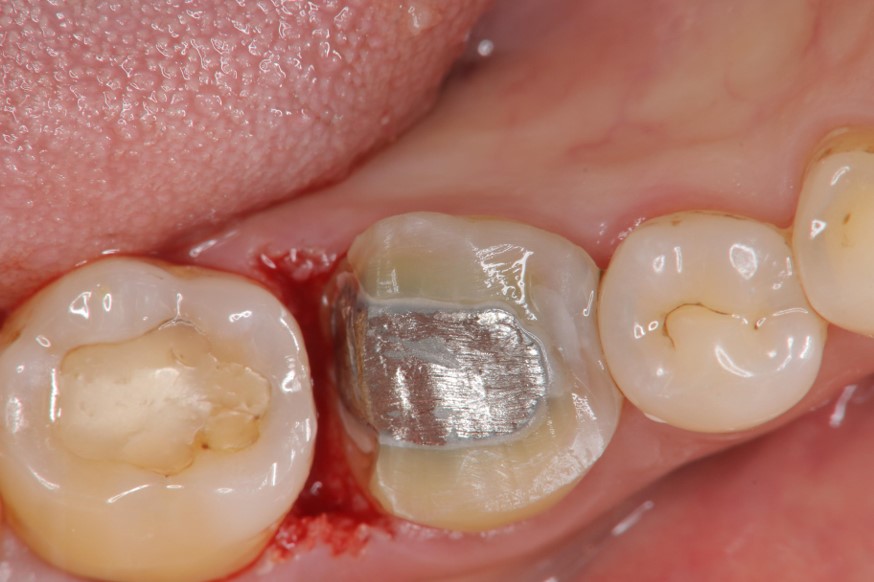

水雷射牙冠增長手術

膺復前評估牙齦、牙齒狀態